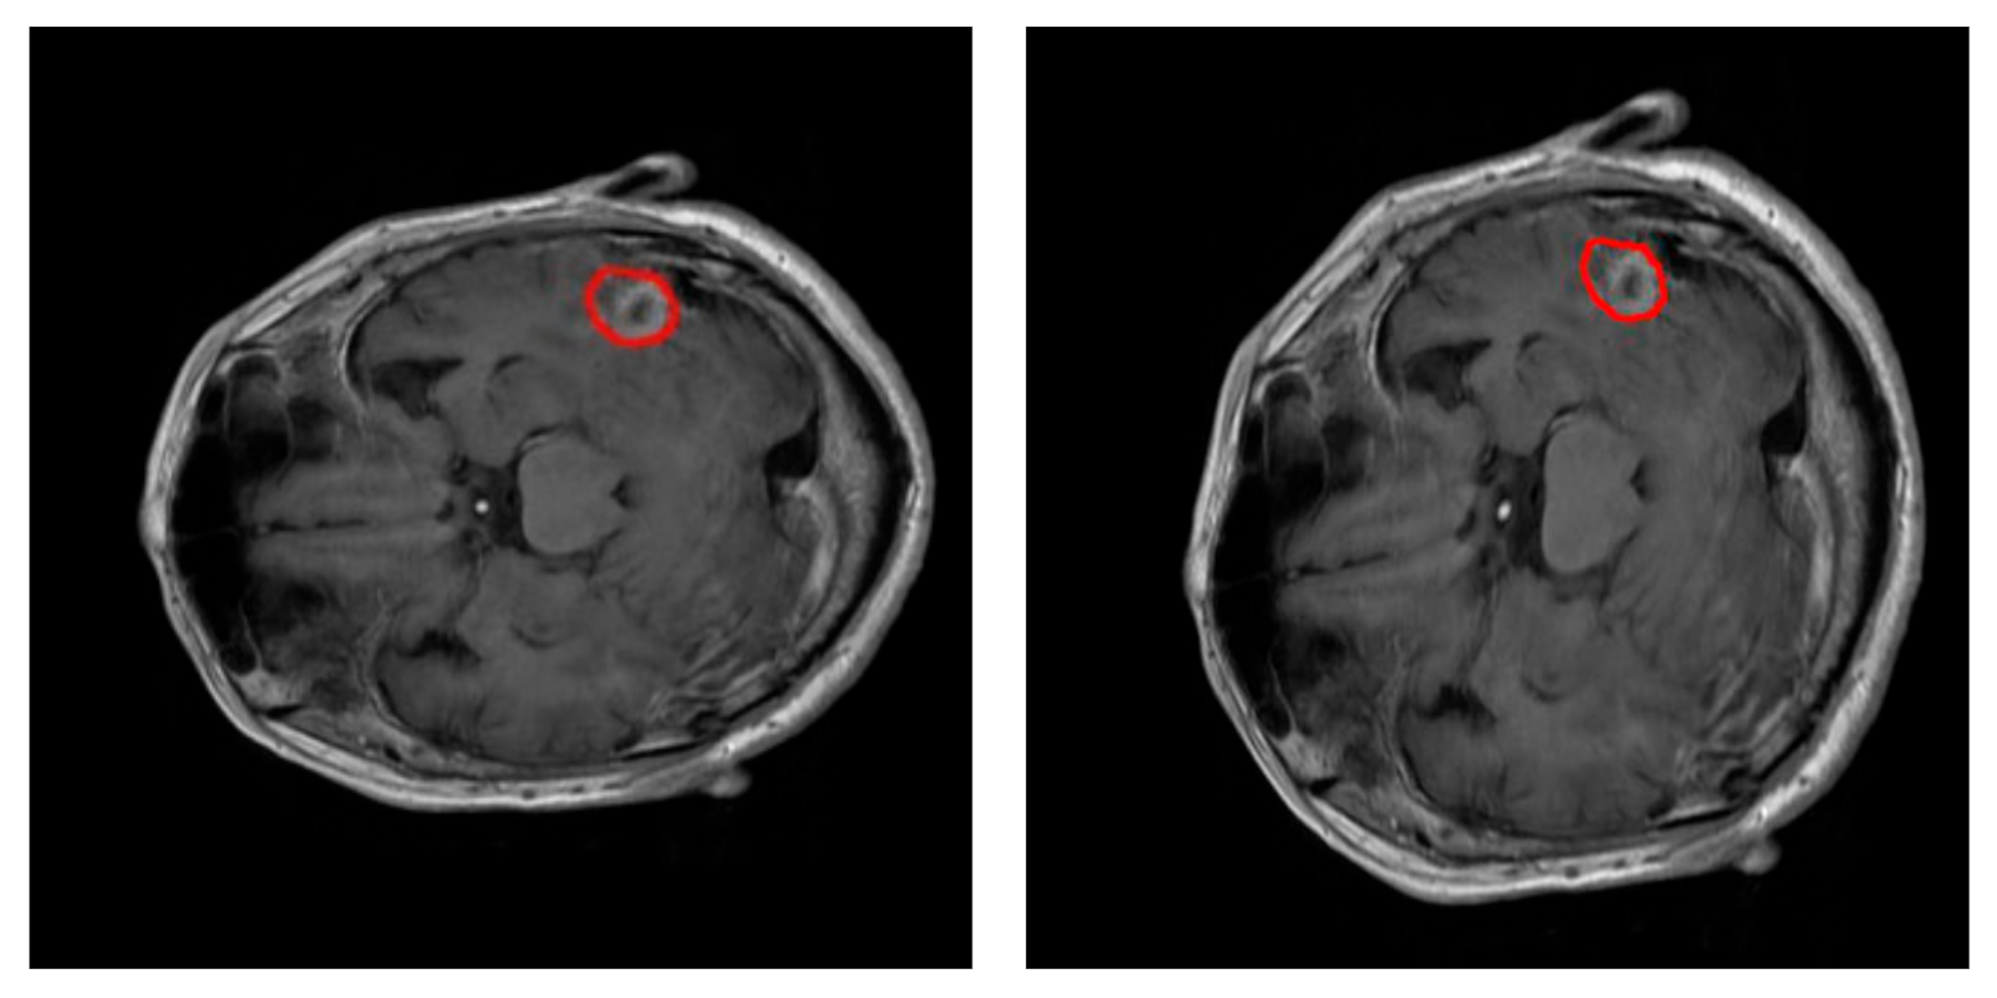

During training, data augmentation using an elastic transform [31] has been used to prevent overfitting of the neural network. Figure 3 shows an example of this transformation. Data augmentation procedure doubled the number of training images available on each fold iteration up to 4904 images. A thorough process was conducted to extract 65 × 65 px training examples from every image in the training dataset: 150 true positive window examples and 325 true negative window examples per tumor. The pixels on these windows were scaled using pixel standardization (zero mean and unit variance) across the entire training dataset.

Figure 3.

Example of elastic transformation used in the data augmentation. Left: original slice. Right: image transformed. In both images, the edges of the tumor have been highlighted in red.